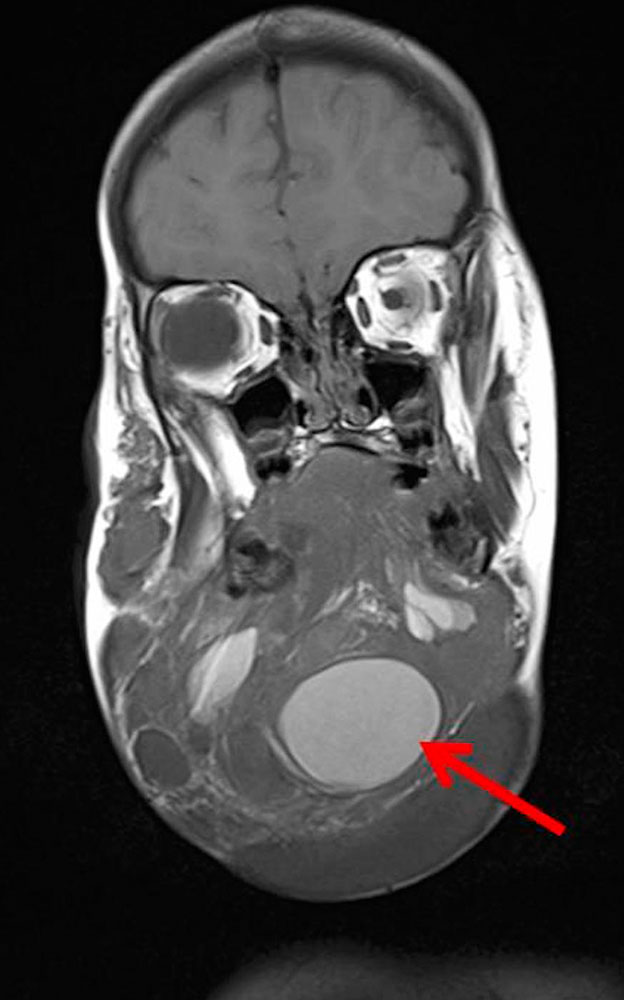

Especially macrocystic LMs can acutely hemorrhage into the cysts, probably via communications with the venous system, which is embryologically closely related to and always communicates with the lymphatic system. Acute hemorrhage results in acute enlargement of the cyst with rapidly increasing space-occupying effects. The cyst then becomes acutely painful and indurated. Especially in the neck area, this can have dramatic consequences for the upper airways.